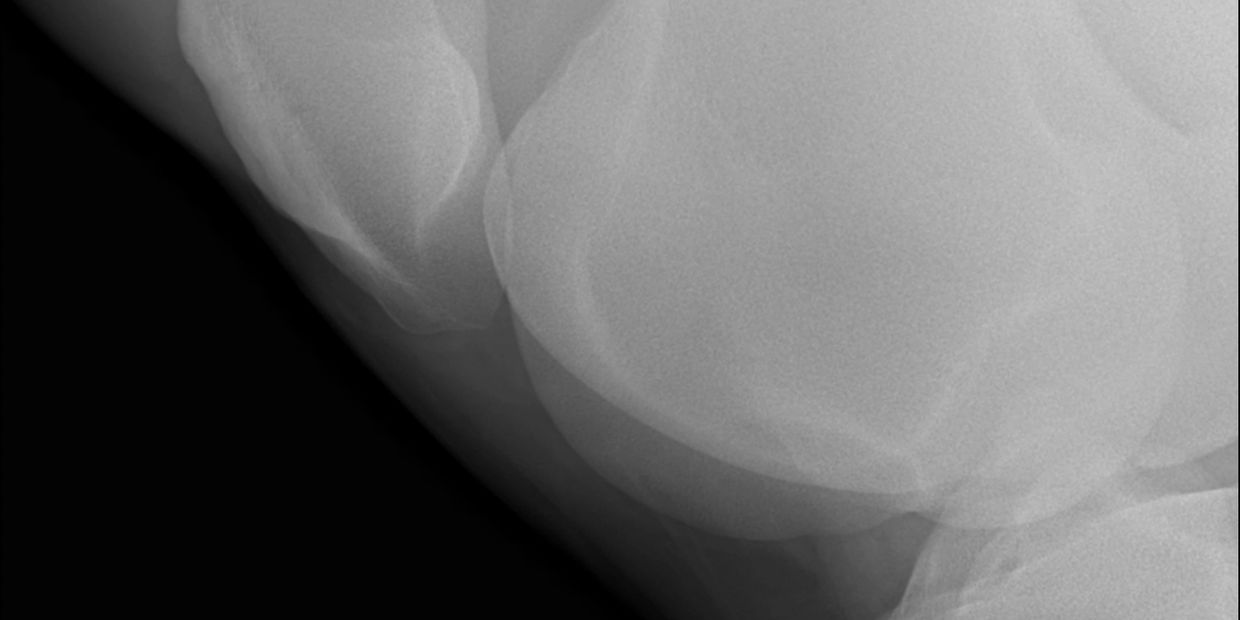

Mid-Michigan Animal Medical Center has a full line of advanced diagnostic equipment including multiple digital X-ray units, ultrasound, upper airway endoscope, and a 3.5M gastrointestinal scope.

Mid-Michigan Animal Medical Center is proud to provide it’s clients with the latest in diagnostic technologies. From digital radiographs to diagnostic ultrasound, we can find the answer you and your horse need.

Wireless digital radiography allows for on-farm developing and viewing of radiographs for instant results and answers.